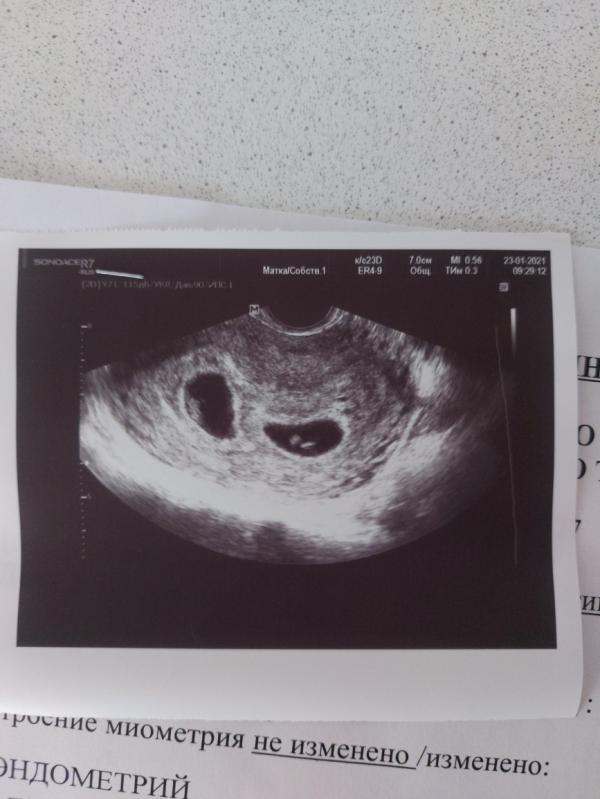

Сегодня сходила на узи 😊

У нас все же будет двойня 🤪 трясет меня,конечно, до сих пор... Если бы это была первая беременность... На третьего я бы,наверное,не решилась. Но....я рада,что у нас будет еще два малыша😁смирилась.